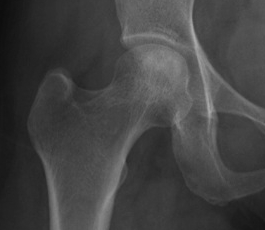

Crescent Sign

- subchondral collapse of the necrotic segment

- separation of subchondral plate from necrotic cancellous bone

Flattening femoral head Crescent sign |

Subchondral fracture IIIA: <2mm flattening IIIB: > 2 mm flattening |

Stage II: sclerosis with cystic areas resorption, no collapse

Stage III: collapse / flattening femoral head with preserved joint space